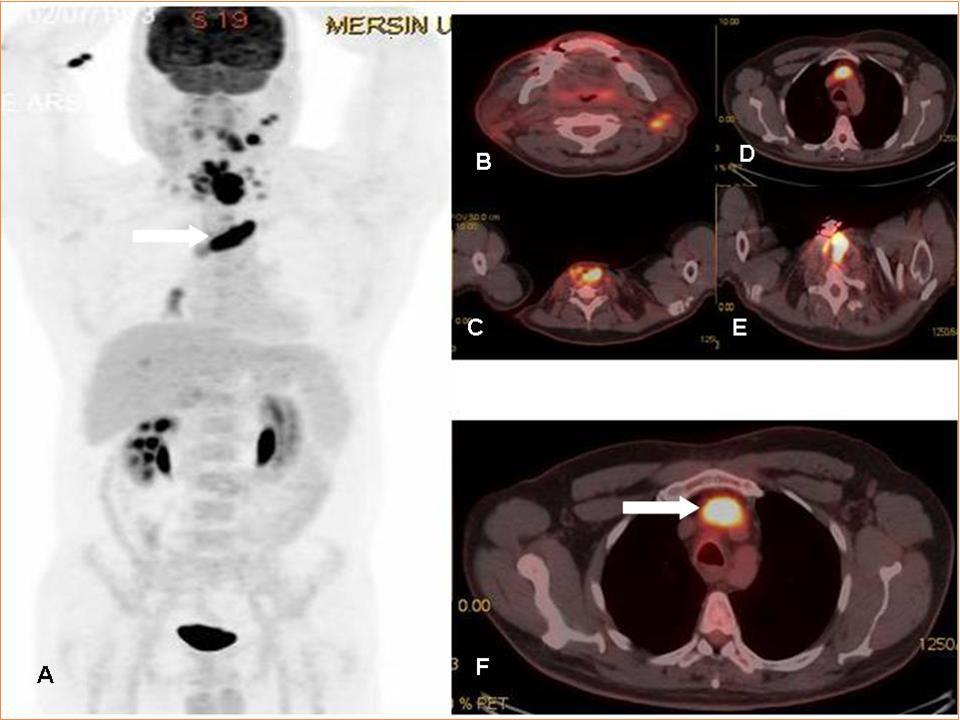

The incidence of thrombus is high in patients with underlying malignancy. This thrombus is mostly venous thromboembolism (VTE), but it may rarely be a tumor thrombus (TT). VTE is common in oncologic patients and is treated with anticoagulant treatment agents whereas aggressive treatment approaches are needed in TT. TT may occur in any cancer and has been reported in many different malignancies (ie, solid carcinomas, sarcomas, and hematologic malignancies) with RCC and HCC being considered the most common underlying malignancies1. In literature, there is only retrospective few articles and some case reports on the role of FDG PET-CT imaging 2, 3, 4, 5, 6. The FDG uptake pattern in TT is not yet as conclusively established, but generally, a linear FDG uptake pattern or more focal FDG accumulation has been reported in literature 2, 3, 4, 5, 6. In a recent interesting image report from Sonavane SN et al, the authors reported the imaging findings of a patient with RCC where PET/CT not only ruled out locoregional adenopathy and distant metastases, but also distinguished tumor thrombi from benign thrombi in the same patient 7. Incidental detection of secondary malignancies or occult metastases from primary malignant disease on 18F-FDG PET/CT has been reported previously 8, 9, 10. In this case report, FDG PET-CT imaging was very useful for diagnosis of tumor thrombus in a patient that diagnostic CT scan could not distinguish tumor thrombus & venous thrombus (Figure 1 A-F).

Figure 1.MIP (Maximum intensity Projection-A) and axial PET-CT fusion (B-F) images demonstrate recurrent mass lesion, metastatic lymphadenopaties and tumor thrombus (white arrows).